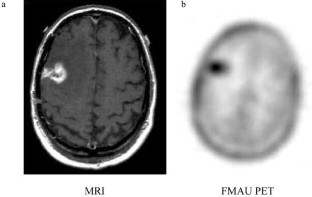

Active tumors in the breast, brain, lung and prostate were clearly visualized with standardized uptake values (SUVs) of 2.19, 1.28, 2.21, and 2.27–4.42, respectively. Unlike with other tracers of proliferation, low uptake of [18F]FMAU was seen in the normal bone marrow (SUVmean 0.7), allowing visualization of metastatic prostate cancer (SUV 3.07). Low background was also observed in the brain, pelvis, and thorax, aside from heart uptake (SUV 3.36–8.78). In the abdomen, increased physiological uptake was seen in the liver (SUV 10.07–20.88) and kidneys (SUV 7.18–15.66) due to metabolism and/or excretion, but the urinary bladder was barely visible (SUVmean 2.03). On average, 95% of the activity in the blood was cleared within 10 min post injection and an average of 70% of the activity in the urine was intact FMAU at 60 min post injection.

Tumors in the brain, prostate, thorax, and bone can be clearly visualized with FMAU. In the upper abdomen, visualization is limited by the physiological uptake by the liver and kidneys.